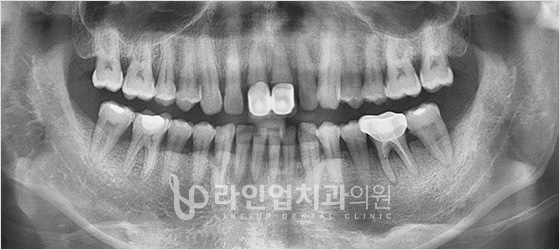

치료전 Before

치료후 After

上臼齿种植牙